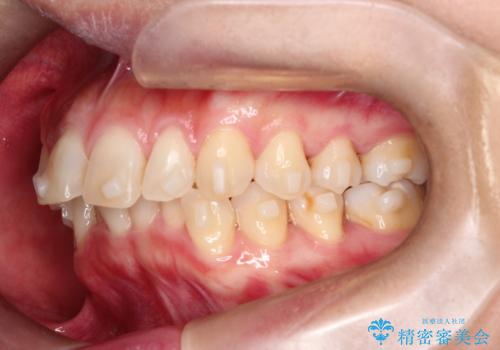

【インビザライン】前歯の凸凹を治したい

- 前歯の凸凹を主訴に来院されました。

臼歯部の遠心移動を行いながらスペースを作り、インビザラインにて前歯をきれいに並べることができました。

今回の治療計画では臼歯部の遠心移動とIPRを行っています。